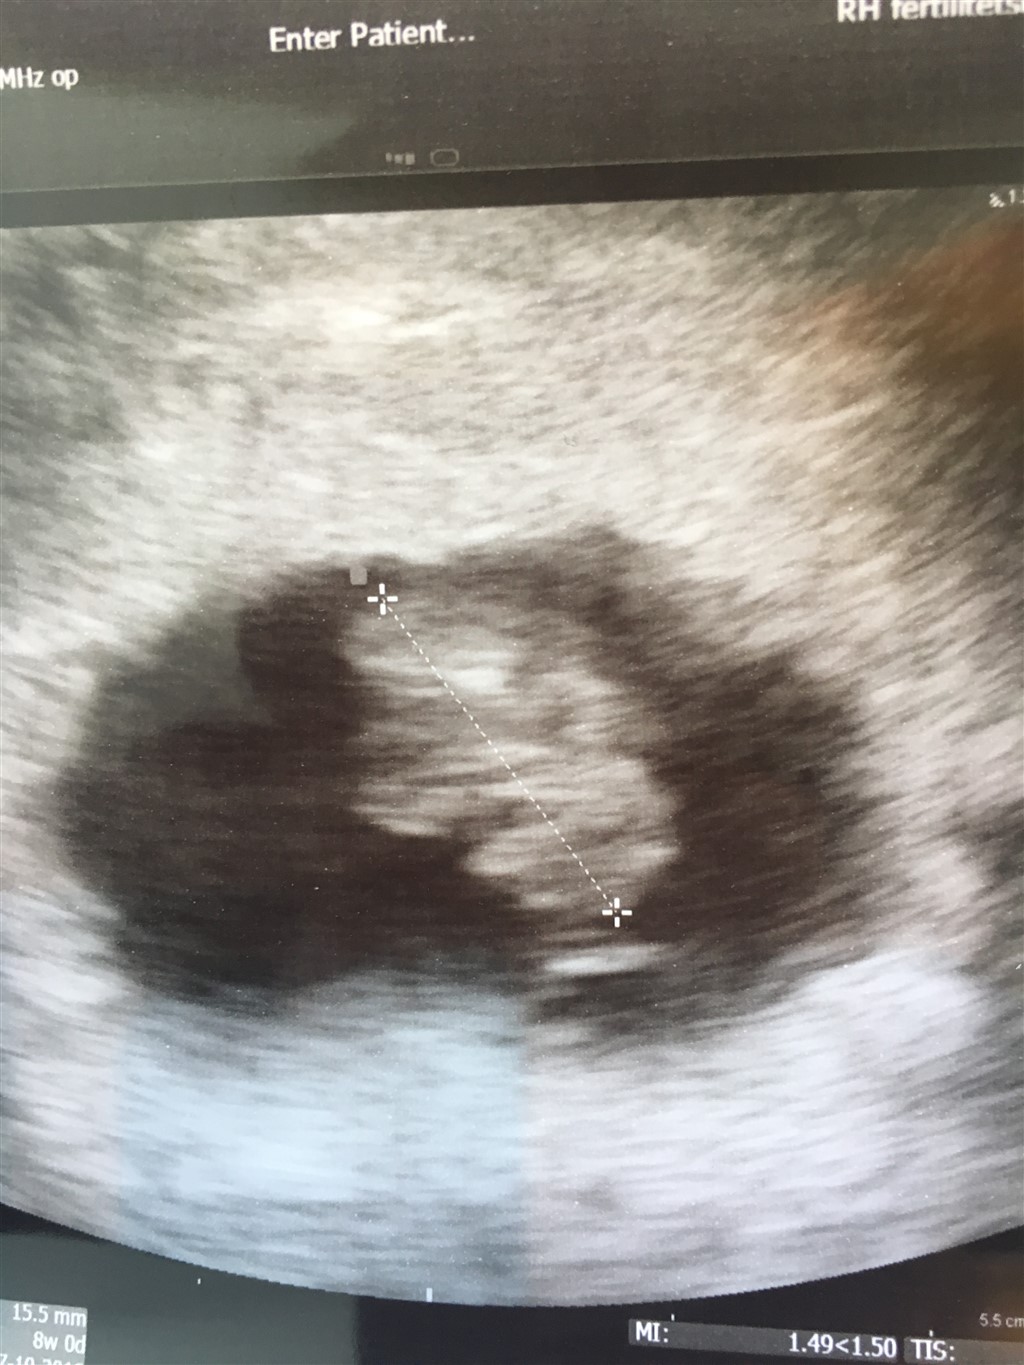

Baby var 15,5 mm og blev sat en dag frem så er i dag 8+0.

I kan lige få et billede af efterårsbønnen der forventes en gang i oktober